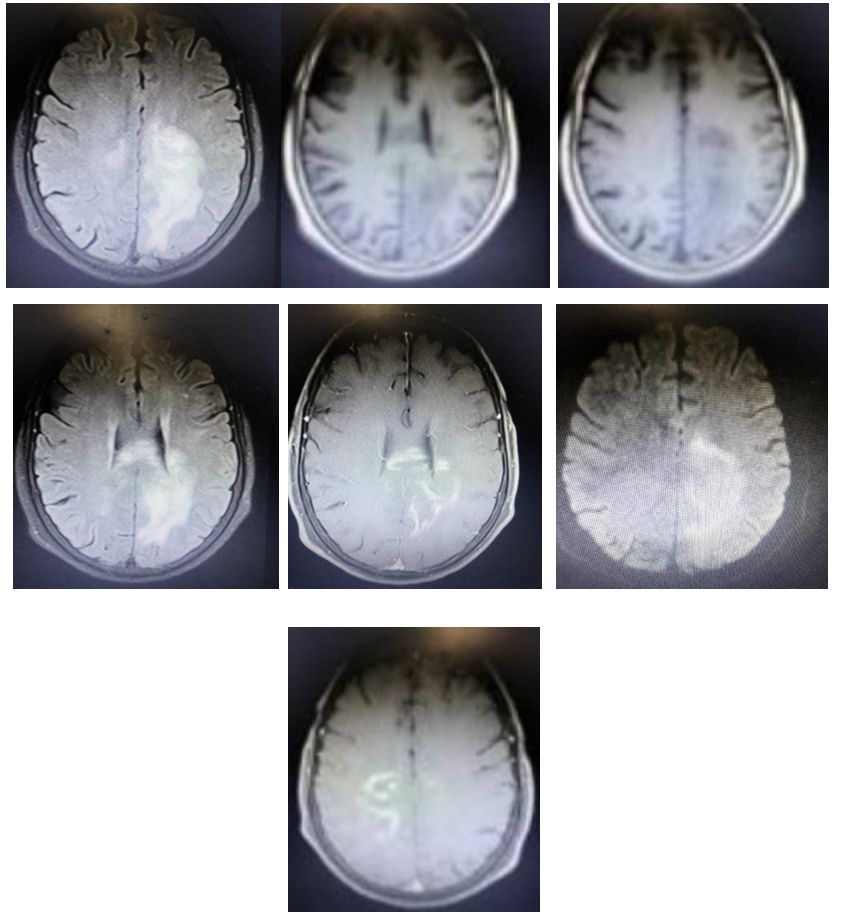

T2序列可见,双侧皮层下及深部白质高信号,融合成片。U形纤维亦有波及。

诊断: 苯中毒脑病。

影像学表现是较为典型的“葵花征”,大家看像吗?

苯中毒诱发的白质脑病在各地广泛存在而且比较常见,然而,缺乏特异性临床表现及实验室检查使其诊断困难。神经影像及有关病史常常是诊断中至关重要的。在本例中,甲苯中毒诱发的白质脑病患者出现恶化的认知损害, MRI T2加权像上呈现出向日葵样的特征性表现。甲苯吸入所致中枢神经系统损害是中毒诱发白质脑病中常见的来源之一。报道的症状多不具特异性,如头痛,头晕,认知损害。在没有造血系统损害的情况下,甲苯中毒性白质脑病可能不易诊断。